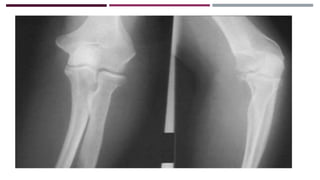

IMAGENOLOGÍA

RADIOGRAFÍA

Obtenida antes de la

reducción

Obtenida después de la

RADIOGRAFÍA Obtenida antes dela reducción Obtenida después de la reducción